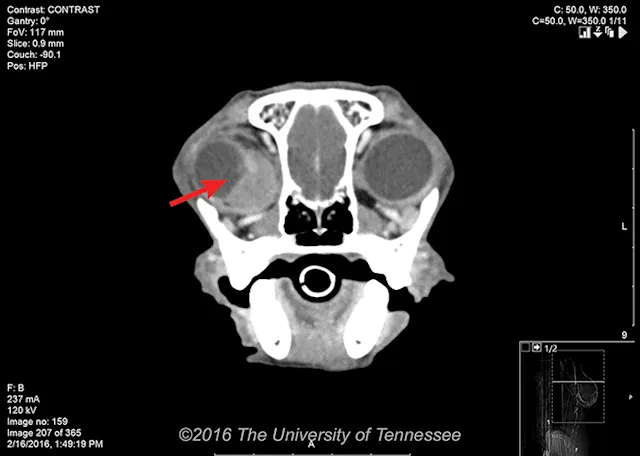

Orbital masses can cause exophthalmia with decreased ocular retropulsion, strabismus, periocular swelling, and elevation of the third eyelid (Figure 1, below). Although nonneoplastic processes (eg, cellulitis, salivary cysts) may occur, many orbital masses are neoplastic, with a reported frequency of 57.6%.2 Patients with cellulitis, such as that seen with a foreign body or orbital abscess, may present acutely and appear painful, whereas patients with neoplasia may have a more chronic history, typically with little discomfort until later stages of the disease process.

FIGURE 1

Marked exophthalmia with dorsolateral deviation of the globe, periocular swelling, and elevation of the third eyelid in an 8-year-old spayed Vizsla with adenocarcinoma of the right orbit